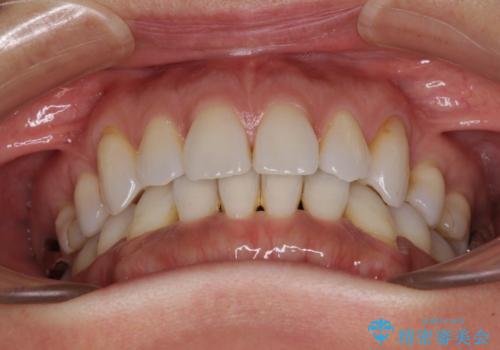

抜歯矯正の後戻りをインビザライン・ライトで解消

- 下顎前歯を中心に、以前行った矯正治療の後戻りが気になるとのことで来院された患者様です。

後戻りは軽度であったため、インビザライン・ライトにて治療を行うこととしました。

矯正治療後は、再度後戻りすることを極力回避するために、下顎前歯の舌側を細いワイヤーを用いて保定することとしました。